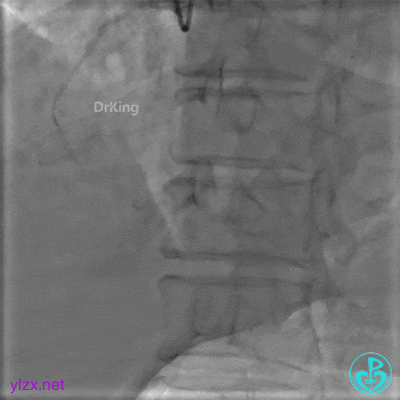

封堵后造影,PL分支远端血流中断。

心包内无明显积液。